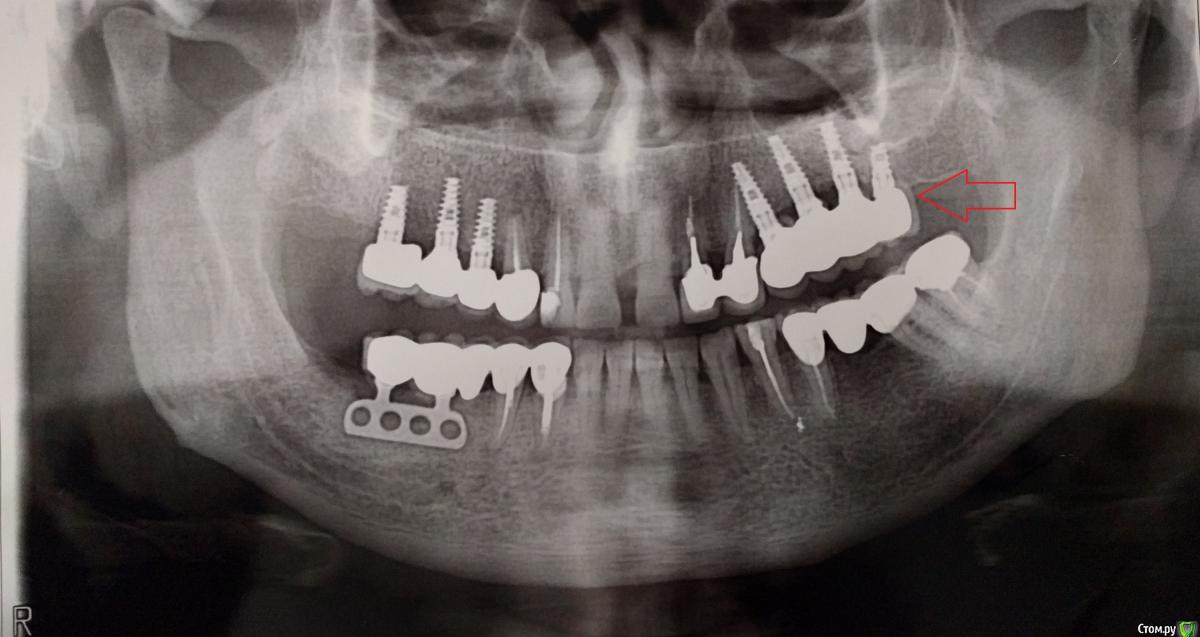

pistons777 Опубликовано 17 ноября, 2018 Поделиться Опубликовано 17 ноября, 2018 Здравствуйте, 3 года назад были установлены в верхнюю челюсть 4 импланта с наращиванием кости.Через 6-7 месяцев был установлен мост.2 месяца назад (мост начал слегка шататься (дышать, почвакивать…)Обратился к доктору, сделали снимок который показал, что импланты в порядке и скорее всего отклеился мост, попытались снять мост, но безуспешно.После чего было принято решение ждать, чтоб больше расшатался мост.Спустя месяц, мост стал намного больше шататься, но снять не получилось т.к. при попытке вытащить, его как будто клинит.Теперь стоит вопрос распилить мост и разбираться, что произшло.Если проблема с абатментом или абатментами нужно знать производителя, а он неизвестен т.к. устанавливались одним доктором, а другой доктор сейчас решает эту проблему. Так сложилась ситуация, географически. Спасибо, за вашу помощь! Ссылка на комментарий

Nazim_NV86 Опубликовано 18 ноября, 2018 Поделиться Опубликовано 18 ноября, 2018 Здравствуйте. Систем имплантации сейчас сотни. Журнал операций должен быть, с датой и наклейками от имплантов. По звонку узнать не пробовали? (Похожи на альфа био spi) 1 Ссылка на комментарий

Bier Опубликовано 19 ноября, 2018 Поделиться Опубликовано 19 ноября, 2018 имплантаты похожи на израильские. Там почти у всех систем стандартно все. Alpha-Bio как вариант. Ссылка на комментарий